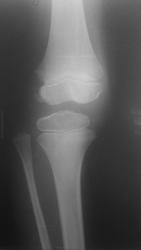

Мальчик 11 лет, жалобы на боли в коленных суставах в утреннее время. Движения в полном объеме, безболезненные, варусная деформация голеней с обеих сторон. У отца и деда выраженый гоноартроз.

Вопрос к детским рентгенологам (сама с детьми не работаю)-"лохматость" контуров суставных поверхностей бедренных костей у деток должна быть? А потом мне какие дополнительные тени кажутся, как суставные мыши у взрослых.

Костная структура соответствует возрастной норме. Единственное, что настораживает, великоват диастаз в межберцовом сочленинии. Я бы выполнила сравнительную рентгенографию обоих коленных суставов в прямой проекции с очень небольшой внутренней ротацией голеней 1 лучом на 1 пленке (с обязательным строгим соблюдением симметрии в укладке).

Костный возраст не соответствует 11 годам, по Садофьевой:

Полное окостенение эпифизов бедренной, большеберцовой и малоберцовой костей завершается несколько раньше (примерно в 8 лет)

Головки малоберцовок - как-то высоковато стоят по прямым снимкам, то ли укладка такая.

Согласна, суставы не соответствуют возрасту, дополнительные тени - это добавочные ядра окостенения. Малоберцовые кости какие то длинные, щели межберцовых суставов широкие (в норме малоберцовая кость накладывается на большеберцовую). Вообщем, какие то диспластичные суставы. Костно-травматических изменений нет.

подозрение здесь на 2сторонний рассекающий остеохондрит ,ко-ый может иметь место в 30% случаев .слева в проекции дистального эпифиза бедра ,в проекции латерального мышелка бедра ,определяются точки окостенения ,один из находится на большом удалении от мышелка,чего не должно быть ,вероятнее всего яв-ся костным фрагментом.справа четко определятся костный фрагмент вогнутой формы (ядро окостенения всегда должно быть в этой зоне округлой формы ),с нечеткостью замыкательной пластинки (размытость).решить вопрос может мрт-будет отек и гипоинтенсивный сигнал во всех последовательностях(участок некроза)